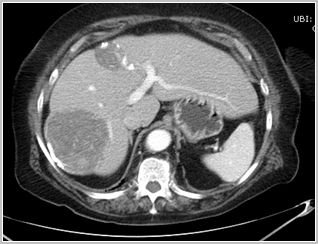

2.- La TC es mejor para mostrar la calcificación de la pared del quiste, y descartar complicaciones pre y postquirúrgicas (signos de sobreinfección del quiste o siembra peritoneal). Se puede usar como técnica inicial de diagnóstico pero es más útil reservarla como complementaria.

Quistes Hidatídicos hepáticos no complicados con pared parcialmente calcificada